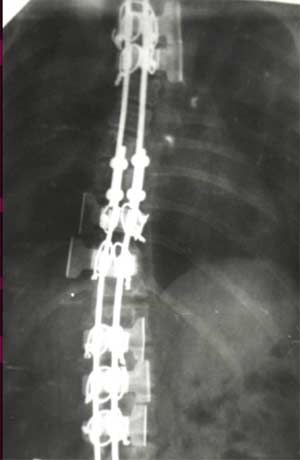

У больных со II степенью деформации

коррекция составила 96,56 - 100%

|

При

сколиозе III степени - 88,19 - 91,26%.

сколиозе IV степени с углом деформации

в диапазоне от 51° до 70° коррекция

составила от 79,2 до 84,8%. С углом от 71° дог

80° - 73,3 - 86,5%. С искривлением от 81° до 122°

удалось достигнуть одномоментно

коррекции в пределах 72,7 - 73,8%.

Коррекция

ротационной деформации при II степени

сколиоза была 61,83%.

При III степени удалось добиться В среднем

коррекции на 59,2%, а при IV степени только

на 34,04%. Более низкий процент коррекции

сколиотической деформации, как боковой,

так и ротационной, объясняется тем, что

как правило оперативному лечению с IV

степенью подвергаются пациенты с

запущенными стадиями заболевания, как

правило с законченным ростом, более

взрослые, с достаточно уже жестким

фиксированным позвоночником. И не менее

важно то, что угол деформации большой,

часто более 80° - 90°, а это при одномоментной

коррекции чревато неврологическими

осложнениями различной степени тяжести.

Для

достижения более полного эффекта

коррекции в момент операции при тяжелых

степенях сколиоза с выраженной реберной

деформацией мы дополнительно прибегаем

к торакопластике на вершине искривления.

При этом производится остеотомия ребер

с частичной их резекцией. Т.е. совмещаем

две операции: коррекция сколиотической

деформации и торакопластика реберного

горба. Кроме этого эффективность

коррекции при тяжелых степенях повышает

и увеличение жесткости пластин, что

достигается использованием не двух

пластинчатых корректоров, а трех- и

четырех пластинчатых. Причем, комбинация

установки пластин может меняться в

зависимости от необходимости у конкретного

ребенка. Планирование оперативного

вмешательства и подбор корректора

проводится строго индивидуально для

каждого больного.